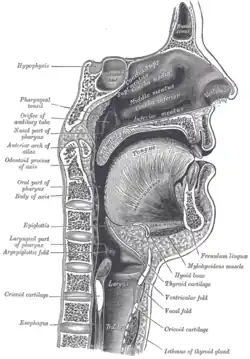

Median sagittal section through the occipital bone and first three cervical vertebra Sagittal section of nose mouth, pharynx, and larynx

Sagittal section of nose mouth, pharynx, and larynx Axis on X-ray